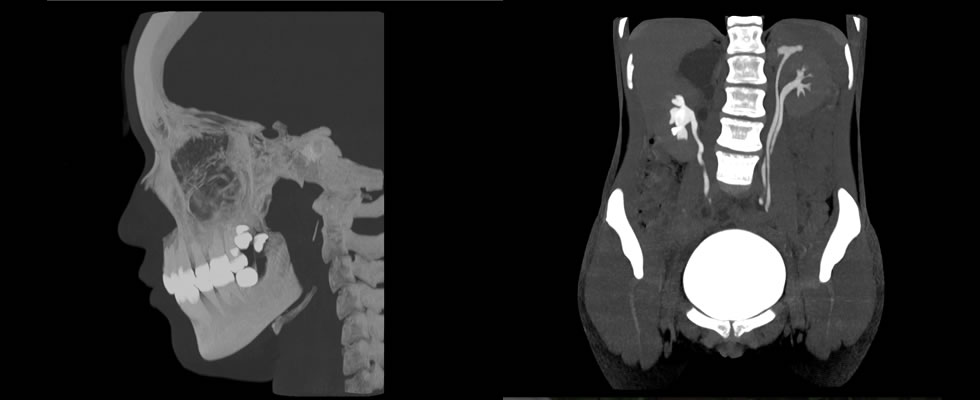

Interpretación de Estudios de Tomografía Multicorte

La interpretación de estos estudios es realizado en estaciones de trabajo que funcionan bajo una plataforma basada en tecnología Apple y el software OSIRIX, que garantiza las herramientas necesarias para la adecuada interpretación de los estudios en las diferentes modalidades, incluyendo los de tomografía multicorte con reconstrucciones en 2D Y 3D. El grupo de médicos Radiólogos encargados de la lectura de tomografías tienen entrenamiento en el área con experiencia laboral en reconocidas instituciones de la ciudad de Cali.